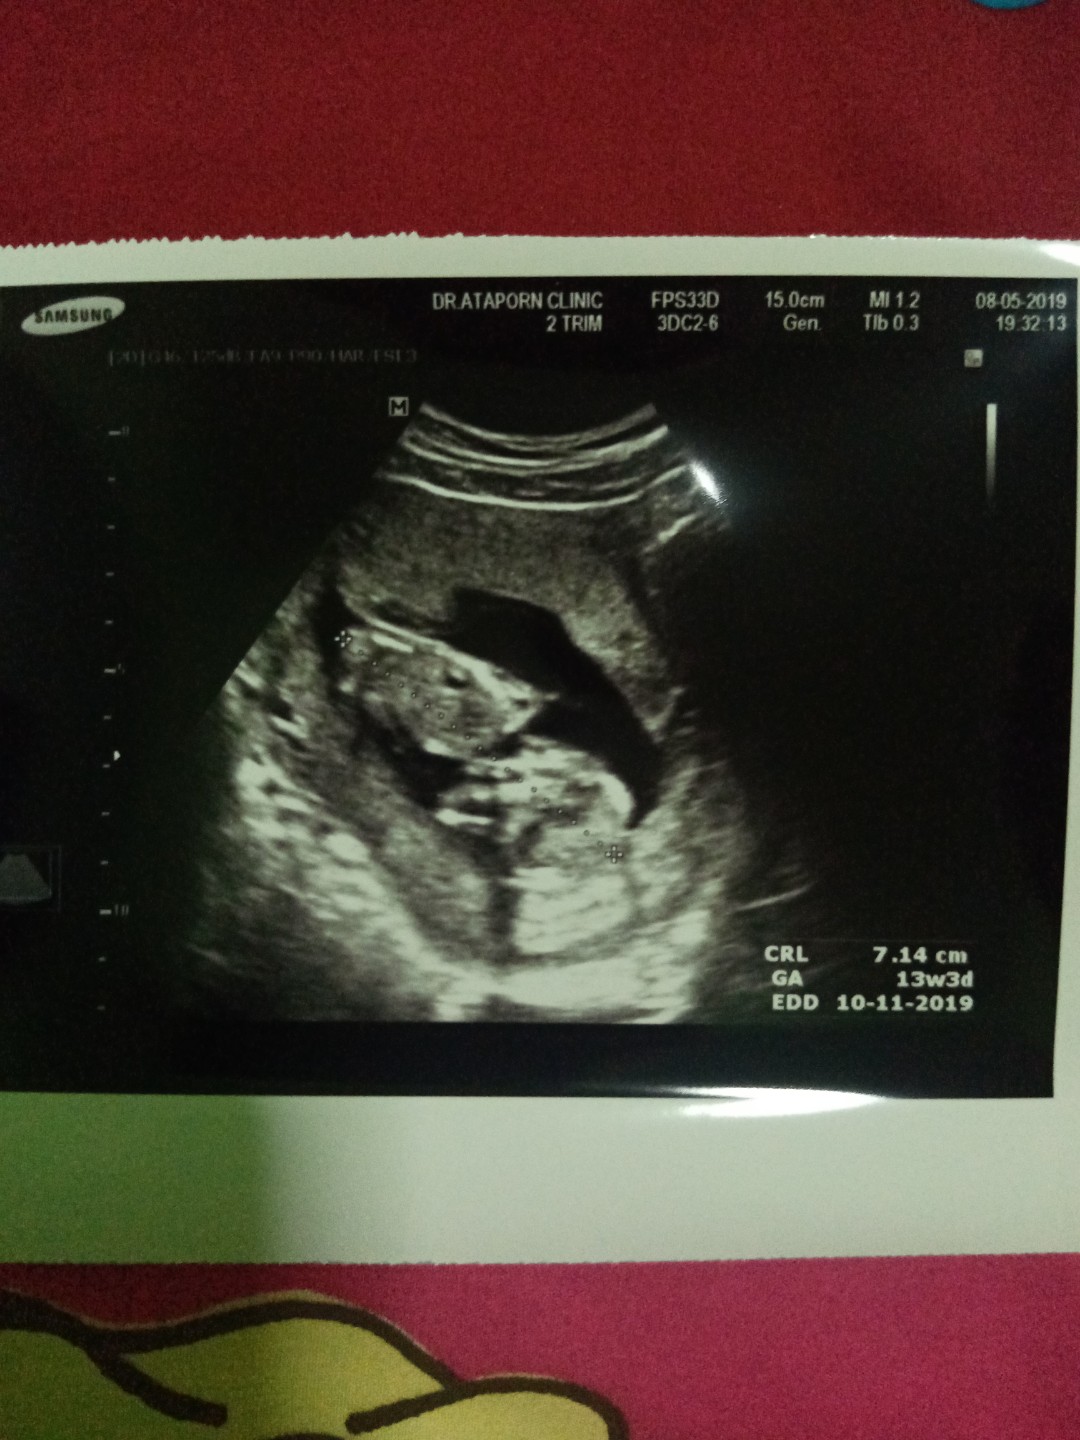

แม่ๆคนไหนมีภาพอัลตร้าซาวด์ประมาณ13วีคบ้างคะ ของเรา13วีค ภาพแบบนี้ค่ะ ดูไม่ออกเลย?

13w3d ตอนนี้21wเเร้วค่ะ